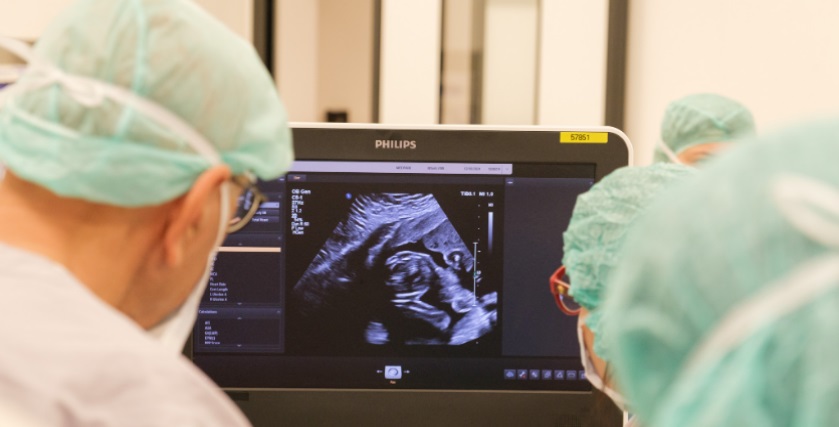

Gândită până la cele mai mici detalii, intervenția se efectuează în sala de operații cezariene, locația fiind dotată cu tot ce este necesar pentru a face față situațiilor imprevizibile. Intervențiile fetale se realizează sub ghidaj ecografic sau prin chirurgie fetoscopică.

După îndepărtarea problemei de sănătate, fătul este verificat ecografic peste estimativ 2 ore de la intervenția propriu-zisă.